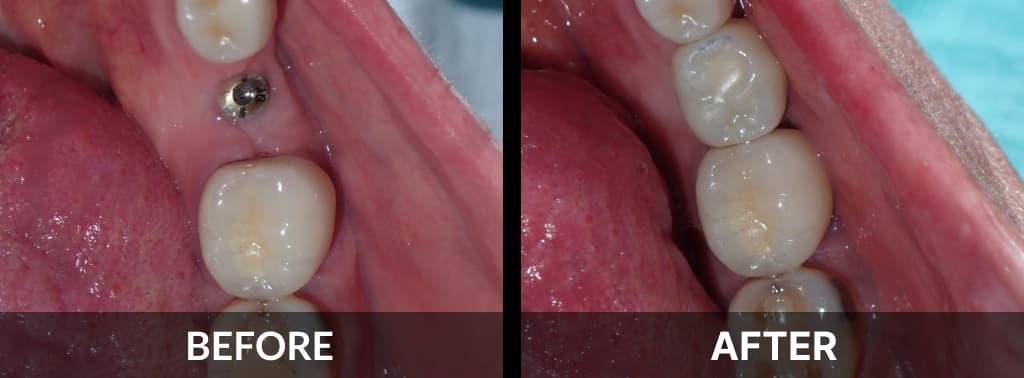

Before and After View

Gallery of Implants

Before After Seat Crown